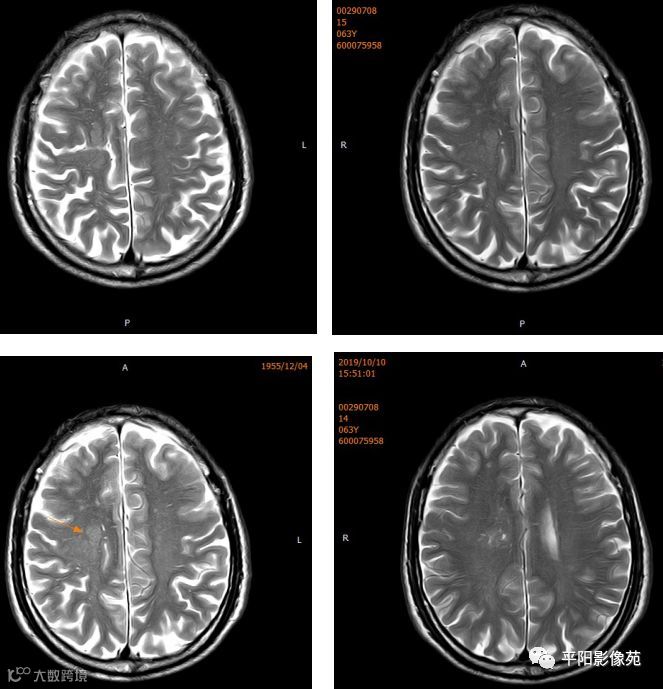

右侧额叶中央前回局部脑裂增宽,并向内延伸,周围衬以等灰质信号,呈稍长T1稍长T2信号,病灶自软脑膜向内延伸,与室管膜相连。